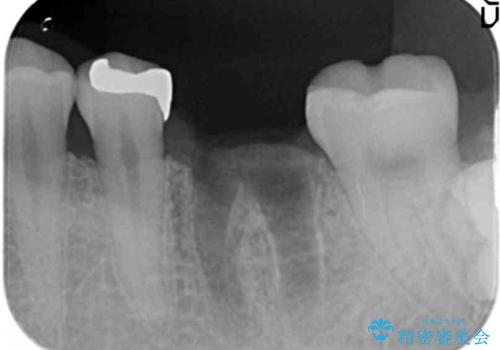

- 銀歯の奥歯で噛むと違和感・痛みがあるとのことで検査・治療を求めて来院されました。

銀歯を除去して見ると内部で虫歯が再発し、歯の辺縁は破折し保存が難しく抜歯をしなければいけない状態でした。

銀歯に限らず神経を除去する根管治療を行なった歯は、痛みが出ないまま虫歯が進行していることもしばしばみられます。

外から見ても状況は全くわからないことが多いため、X線による定期的な検査が重要です。